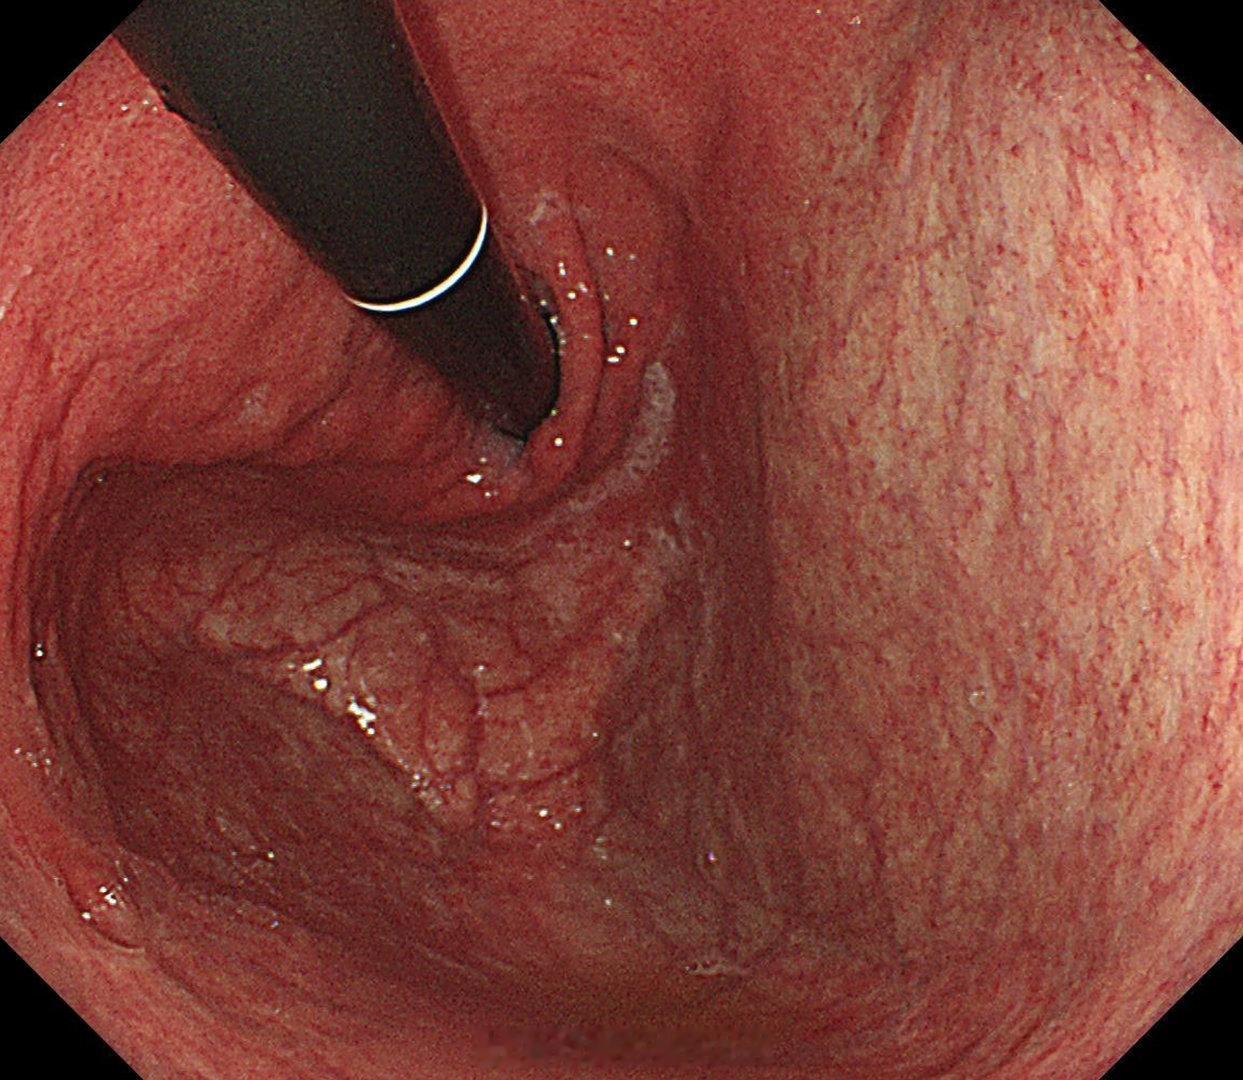

这是个常州来找我会诊的疑难杂症,当地觉得萎缩一塌糊涂,但是活检也没有提示啥病因,一开始我接诊也觉得是自身免疫性胃炎,但是抽血指标都不符合,最后在几块残余正常黏膜表现中看到了点蛛丝马迹,活检加上masson染色确诊是胶原性胃炎,以前不认识的时候这个世界都没这个病,一旦会诊断以后,满眼都是这类病[允悲][允悲][允悲]

这是个常州来找我会诊的疑难杂症,当地觉得萎缩一塌糊涂,但是活检也没有提示啥病因,一开始我接诊也觉得是自身免疫性胃炎,但是抽血指标都不符合,最后在几块残余正常黏膜表现中看到了点蛛丝马迹,活检加上masson染色确诊是胶原性胃炎,以前不认识的时候这个世界都没这个病,一旦会诊断以后,满眼都是这类病[允悲][允悲][允悲]